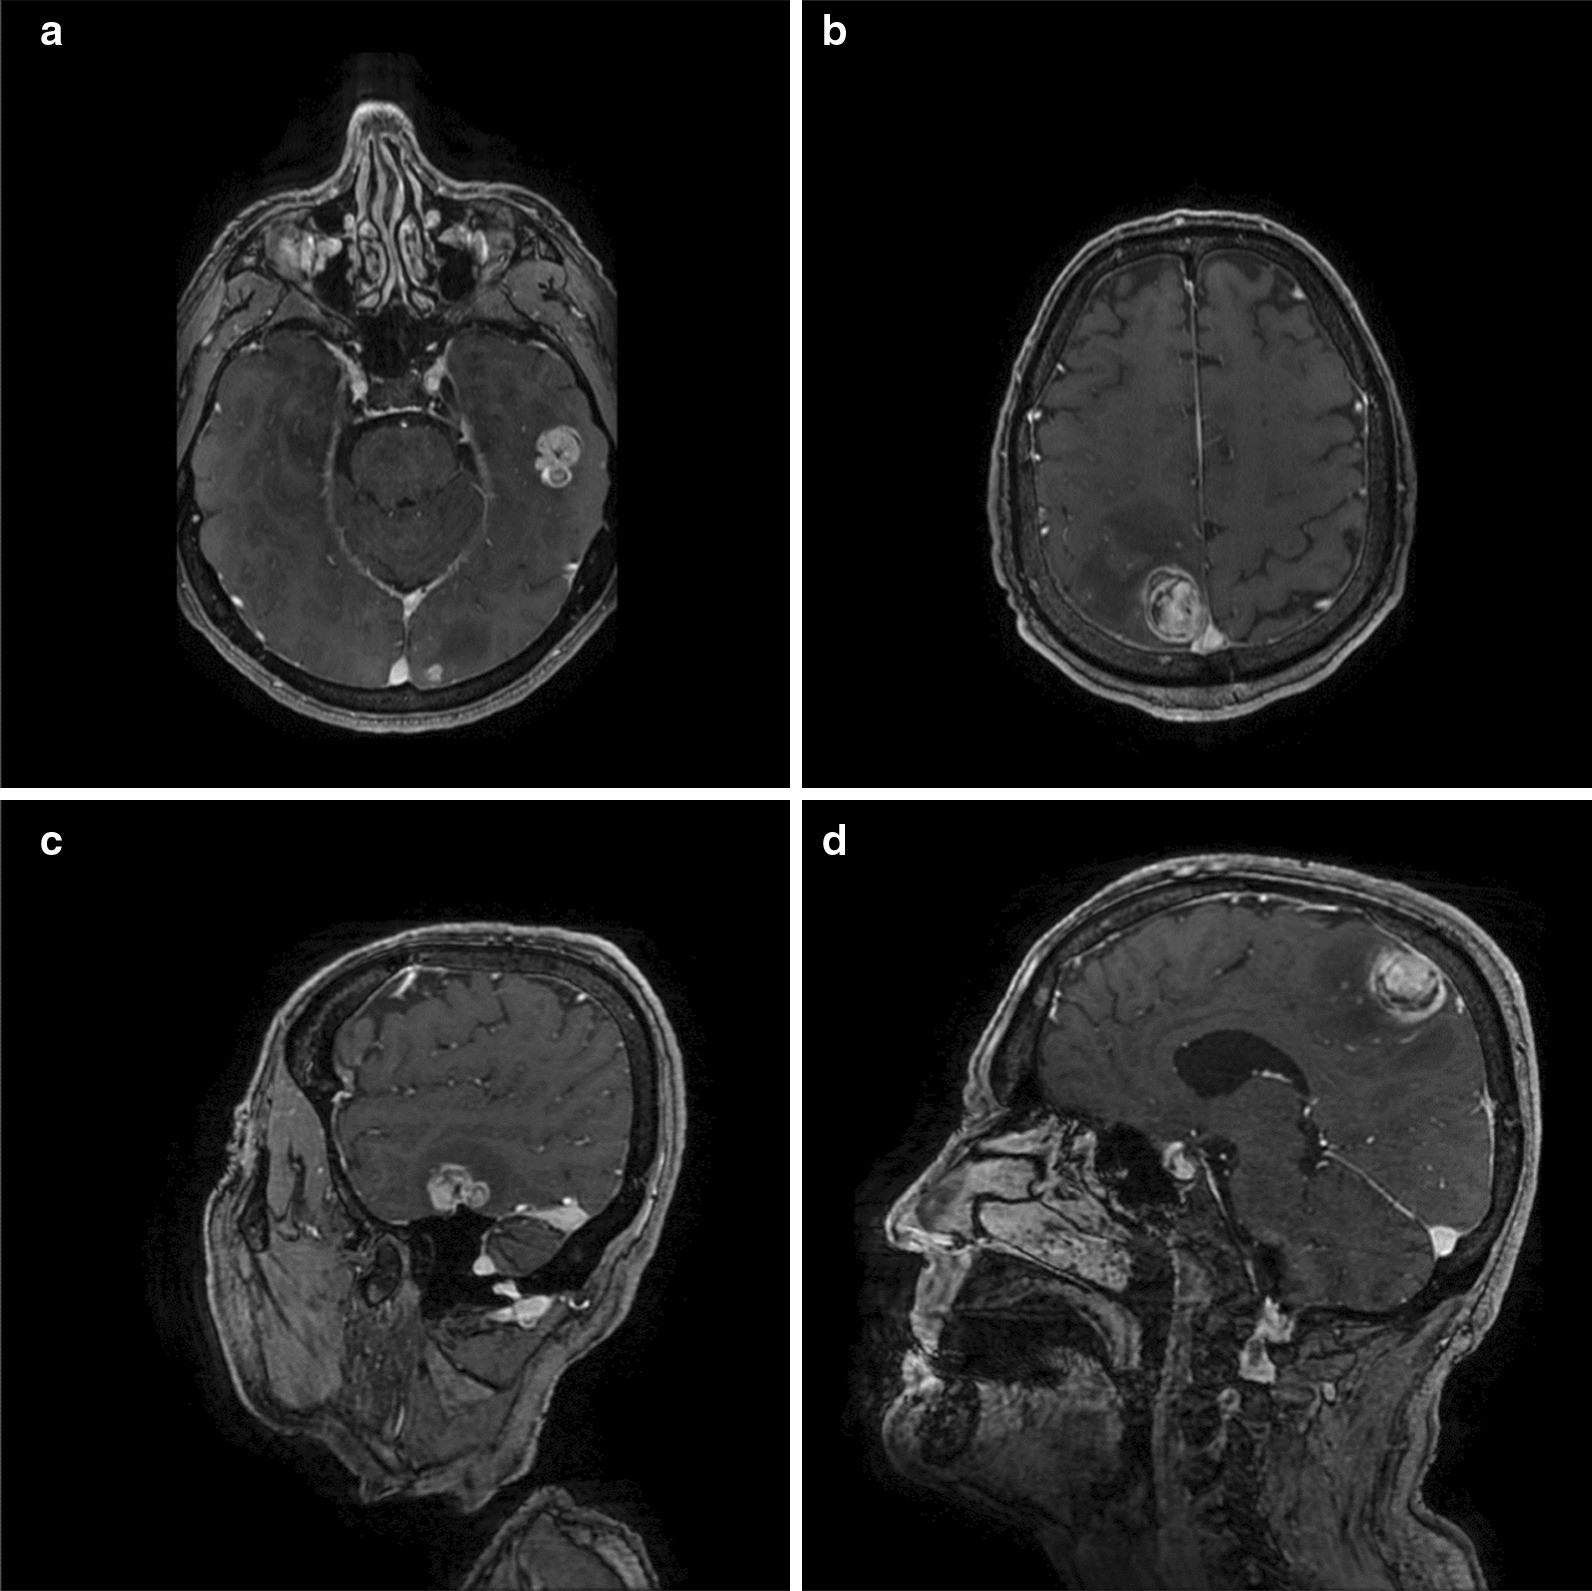

Fig. 1From: A late systemic and brain metastasis from subcutaneous leiomyosarcoma of the right forearm: a case report and review of the literatureContrast-enhanced T1-weighted magnetic resonance imaging scans demonstrating left temporal (a, c) and right parietal (b, d) metastases of leiomyosarcoma (a+b axial; c+d: sagittal)Back to article page